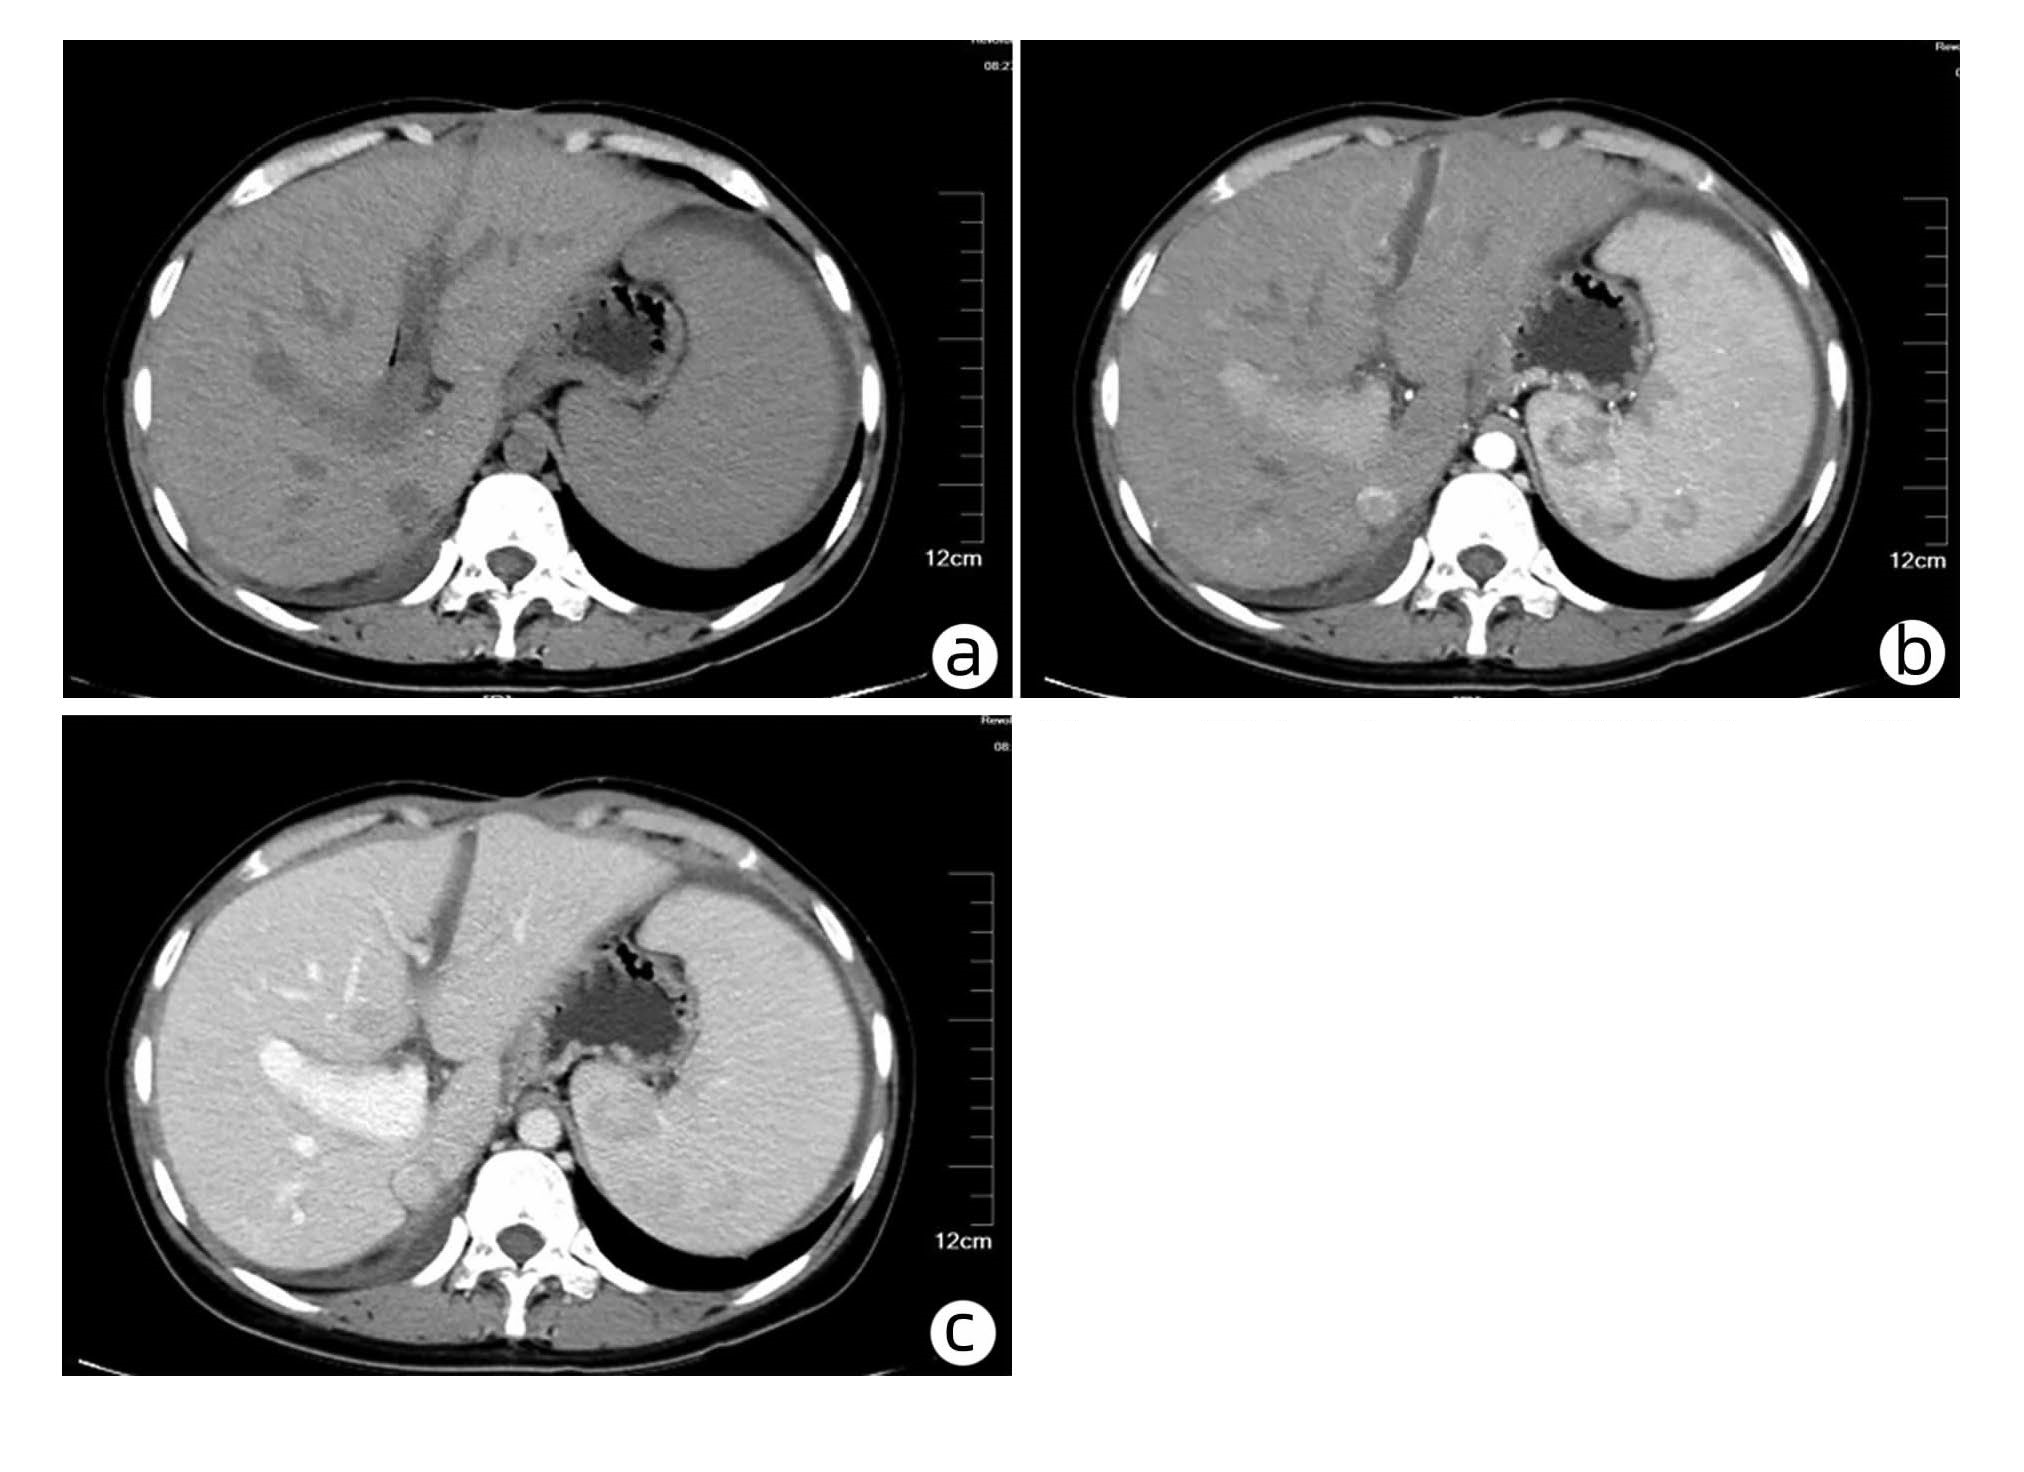

微波消融联合全身化疗治疗复发性肝内胆管癌的有效性与安全性分析

魏春, 刘宇, 李波, 蒋鸥

2023, 39(7): 1609-1616. DOI: 10.3969/j.issn.1001-5256.2023.07.015

摘要:

目的  探讨微波消融(MWA)联合化疗与单独MWA治疗复发性肝内胆管癌(RICC)的有效性和安全性。  方法  采用回顾性队列研究方法。选取2014年1月—2021年3月内江市第二人民医院及西南医科大学附属医院接受MWA+ 化疗和单独MWA的RICC患者,收集入组患者的临床病理资料。计量资料两组间比较采用成组t检验,计数资料两组间比较采用χ2检验和Fisher精确检验。釆用Kaplan-Meier法计算无进展生存期(PFS)和总生存期(OS)。使用Log-rank检验方法比较生存差异。应用单因素和多因素Cox比例风险回归模型分析生存预后的危险因素。  结果  共筛选到106例RICC患者,其中MWA+化疗组55例,MWA组51例。至随访截止,MWA+化疗组的中位PFS为15.0个月(95%CI:14.5~15.5),MWA组中位PFS为13.4个月(95%CI:11.6~15.2),两组差异有统计学意义(χ2=9.624,P=0.002)。MWA+化疗组的中位OS为21.0个月(95%CI:20.0~21.8),MWA组中位OS为18.0个月(95%CI:16.3~19.7),两组差异有统计学意义(χ2=12.784,P<0.001)。Cox回归分析显示,肿瘤直径(HR=0.425, 95%CI:0.208~0.868,P=0.019;HR=0.299, 95%CI:0.121~0.739,P=0.009)、复发时间(HR=7.064, 95%CI:3.612~13.618,P<0.001;HR=2.341, 95%CI:1.072~5.113,P=0.033)及联合化疗(HR=0.138, 95%CI:0.069~0.276,P<0.001;HR=0.175, 95%CI:0.081~0.380,P<0.001)是RICC患者PFS和OS的独立影响因素。两组常见不良反应中,除血液学毒性发生率(χ2=12.524,P<0.001)外,其余不良反应发生率差异均无统计学意义(P值均>0.05)。  结论  与单独MWA相比,MWA+化疗可以改善RICC的预后,延长其PFS和OS,且副反应安全可控。肿瘤直径>5 cm、复发时间<1年、未联合全身化疗的患者预后不良。